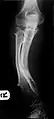

It is characterized by the growth of cartilage-capped benign bone tumours around areas of active bone growth, particularly the metaphysis of the long bones. Typically five or six exostoses are found in upper and lower limbs. Image depicts adult regrowth after knee replacement.

HME can lead to the shortening and bowing of bones; affected individuals often have a short stature. Depending on their location the exostoses can cause problems including: pain or numbness from nerve compression, vascular compromise, inequality of limb length, irritation of tendon and muscle, Madelung's deformity[17] as well as a limited range of motion at the joints upon which they encroach. A person with HME has an increased risk of developing a rare form of bone cancer called chondrosarcoma as an adult.[17] Problems may be had in later life and these could include weak bones and nerve damage.[18][19][20] The reported rate of transformation ranges from as low as 0.57%[13] to as high as 8.3% of people with HME.[21] Some authors have described an association between HME and the presence of popliteal pseudoaneurysms.[22]

The diagnosis of HMO is based upon establishing an accurate correlation between the above-mentioned clinical features and the characteristic radiographic features. Family history can provide an important clue to the diagnosis. This is supplemented by testing for the two genes in which pathogenic variants are known to cause HMO namely EXT1 and EXT2. A combination of sequence analysis and deletion analysis of the entire coding regions of both EXT1 and EXT2 detects pathogenic variants in 70–95% of affected individuals.[3][4] The hallmark of radiographic diagnosis is the presence of osteochondromas at the metaphyseal ends of long bones in which the cortex and medulla of the osteochondroma represent a continuous extension of the host bone. This is readily demonstrable in radiographs of the knees.[3][1]